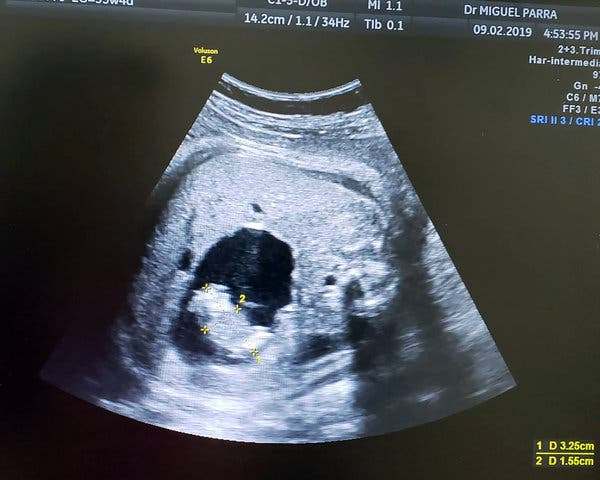

据2019年11月26日《太阳报》报道,在哥伦比亚巴兰基利亚市,孕期妈妈莫妮卡·维格进行超声检查时,医生发现她体内有两根脐带,不仅如此,在婴儿腹中还有一个“囊肿”。

经过仔细观察,医生发现这原来是一个胎儿,有四肢但没有心脏和大脑,且还在不断长大,为一例典型的“寄生胎”。

寄生胎是一种罕见的先天性疾病,遗传学上又称“胎内胎”,发病率在五十万分之一,是指完整胎体的某部分寄生有另一个或几个不完整的胎体。